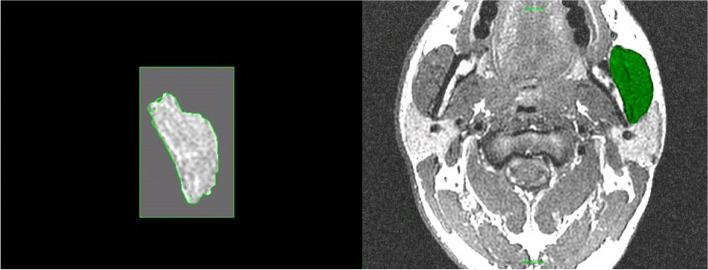

Methods: This investigation was designed to apply several, newly developed and more sophisticated methods of measuring muscle structure and function to a situation where adaptation of muscle is pivotal to the success of a therapeutic approach. Patients attending the combined orthodontic/orthognathic surgery clinic at the Clitrofa - Centro Médico, Dentário e Cirúrgico, in Trofa, Portugal, were screened. Ten patients scheduled for a bimaxillary osteotomy involving a combination of maxillary Le Fort I impaction procedure coupled with a sagittal split advancement of the mandible were selected to form the study group. The patients have MRI of the masseter muscle to evaluate the masseter muscle volume and fibre orientation changes. This exam was taken before surgery (T0), 6 to 12 months after surgery (T1), and 3 years after surgery (T2), by two independent observers, according to the protocol jointly developed between the Eastman Dental Institute - University of London and the MRI Centre - Department of Radiology at John Radcliffe Hospital - University of Oxford.

Results: Significant differences (p < 0.05) have been identified between Time 0 (pre-op) and Time 1 (6-12 months post-op) regarding the masseter area (mm2). The differences against Time 0 (pre-op) seem to disappear at Time 2 (3 years post-op).

Conclusions: MRI therefore seems to be a valid tool for measuring differences in the masseter muscle area and volume associated with high-severity occlusal deformities, although showing not to be as efficient in detecting the same differences in cases of low-severity occlusal deformities.